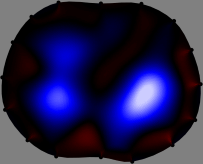

Figs. 3 and 4 compare the performance of the proposed FER method in (20) with the standard regularized least-squares method ((19) when is the identity matrix). The regularization parameter of the standard method was heuristically chosen for its best performance, and the parameter of the FER method was set to be one of three different values . The injection current was 1 mA at 100 kHz, and the frame rate was 9 frames per second. The reference frame at was obtained from the maximum expiration state. The measured data, , represent the voltage differences between each time and . The blue regions, which denote where conductivity decreased by inhaled air, increased during inspiration and decreased during expiration. The FER method with was clearly more robust than the standard method that produced more artifacts originated from the inversion process.